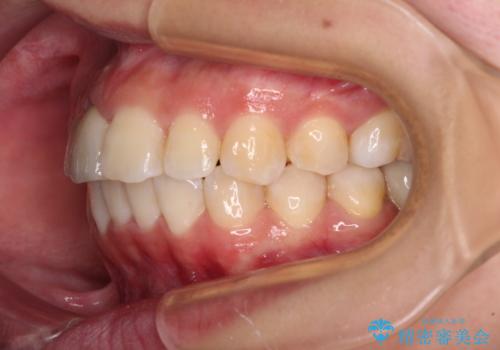

- 放置した虫歯や抜いたままの奥歯、前歯のデコボコを気にして来院された患者様です。

口元の突出感は少なく、下顎の叢生は軽微なものであったので、叢生の強い上顎左右の小臼歯を1本ずつ抜歯し、ワイヤー装置にて矯正治療を行うこととしました。